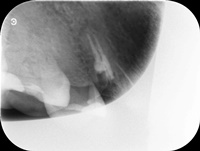

Przed trzema laty ząb 16 (prawa górna szóstka) był przeleczony endodontycznie i wykonano most. W ciągu 18 miesięcy od osadzenia mostu pacjentce kilka razy formował sie ropień dziąsła, osiem razy podawano antybiotyki. Gdy to nie pomagało, wykonano resekcję policzkowego korzenia zęba 16. Nie pomogło. W dalszym ciągu dochodziło do stanów zapalnych i antybiotykoterapii. W tym stanie pacjentka zgłosiła się, do naszego gabinetu. Zdjęto most, przeprowadzono ponowne leczenie kanałowe. Po sześciu miesiącach wykonano nowy most. Upłynęło półtora roku. Nie dochodzi do nawrotów stanu zapalnego, ani obrzęków. Ten przypadek pokazuje, dlaczego tak ważne jest poprawnie wykonane leczenie kanałowe, według nowoczesnego protokołu leczenia.